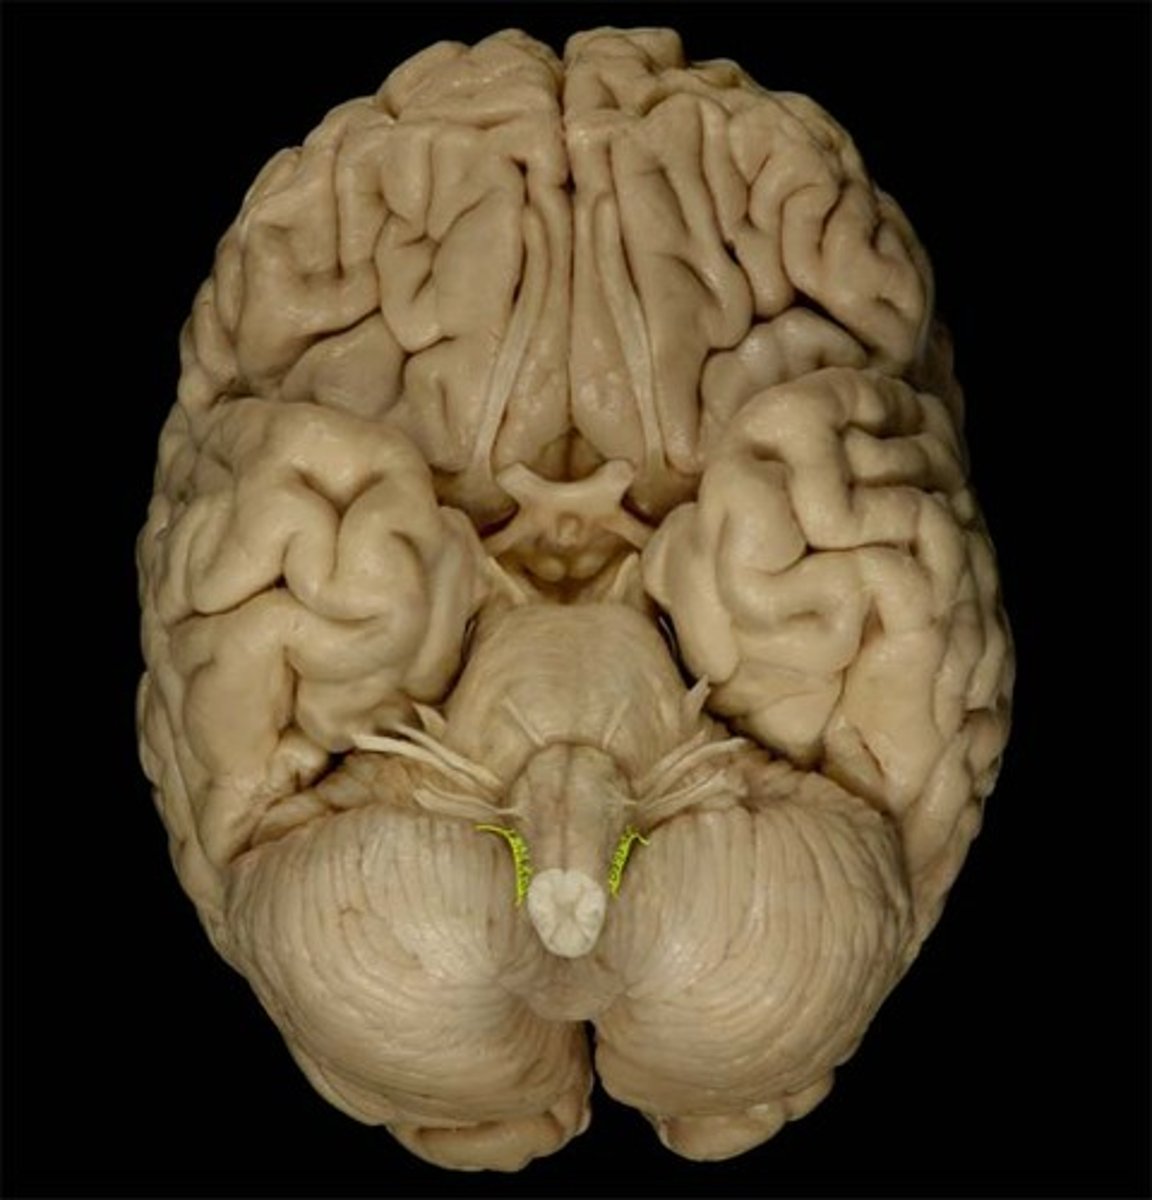

IV Trochlear

motor eye movement